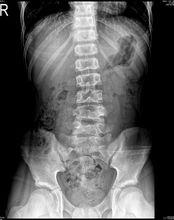

蝴蝶椎是一種脊柱椎體畸形,是椎體的兩個軟骨中心聯合異常,椎體成為左右對稱的兩個三角形骨塊,稱為矢狀椎體裂,在正位X光片上形似蝴蝶的雙翼,故稱蝴蝶椎。如果一側的軟骨中心不發育,則成為半椎體。